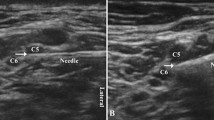

An US-ISB was performed with an injection at the level of the emerging fifth cervical nerve root by a single physician (LS, > 3000 US-guided blocks before starting this study). Under sterile conditions, a linear 18-MHz US-transducer (Focus 400, BK Ultrasound, Herlev, Denmark) and a 22G needle (Sonoplex 50 mm, Pajunk, Geisingen, Germany) were used in an in-plane needle, peri-plexus approach. We performed a peri-plexus approach to avoid subepineural injection, which could damage the root and/or influence our results [28, 29].

The C5 root was localized by identifying the transverse processes of C7, C6 and C5. The needle was positioned lateral and inferior to the C5 root, where 5 mL of the LA was slowly injected after aspiration for blood detection and avoiding intravascular injection.